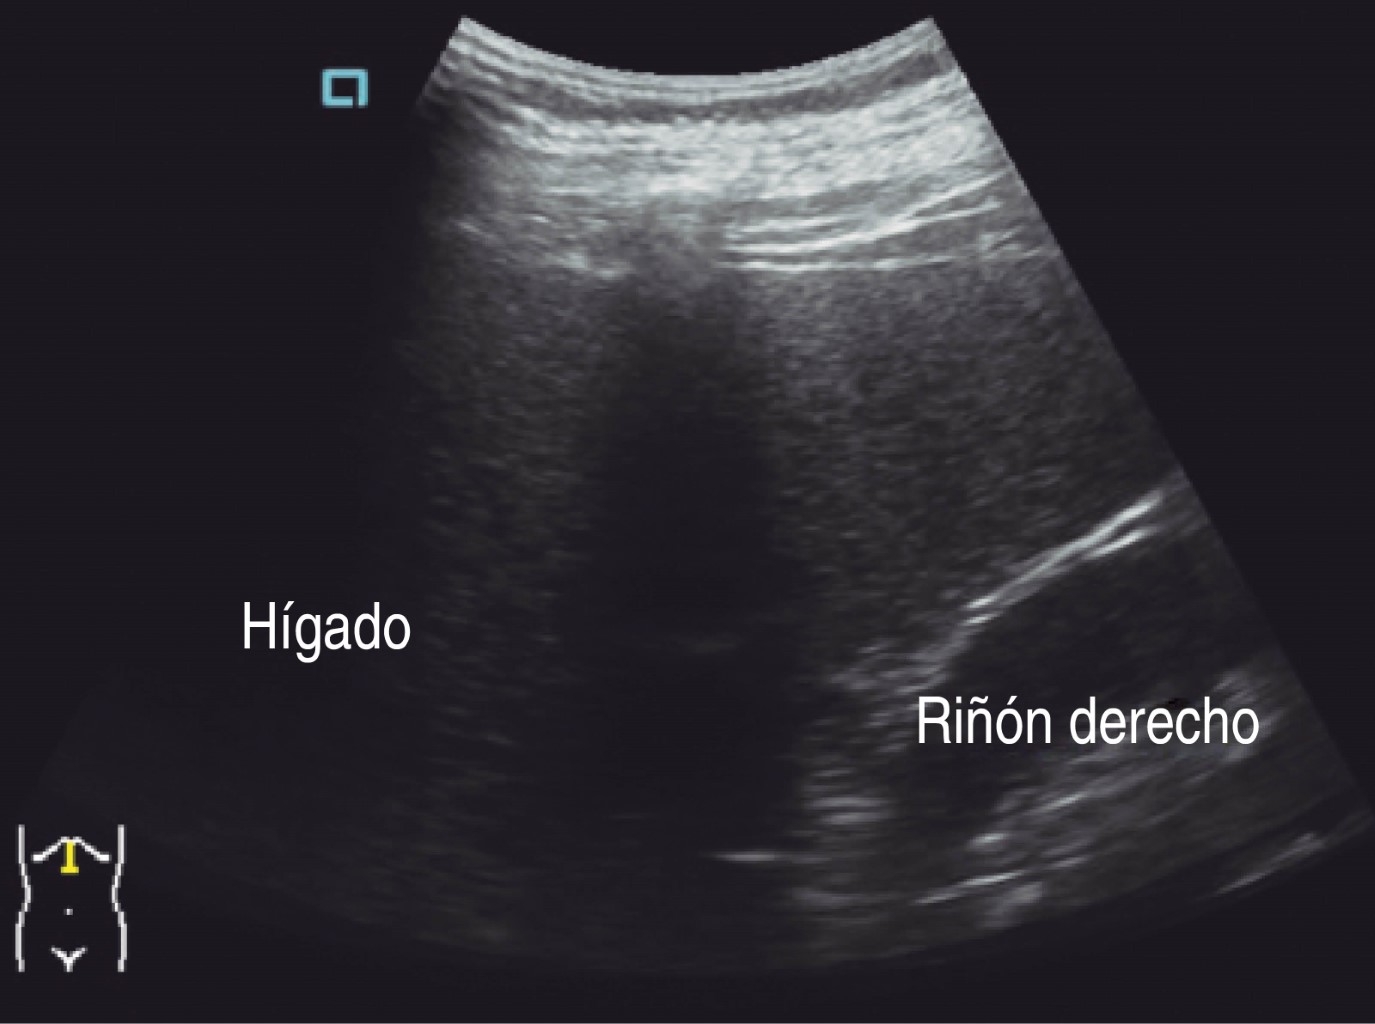

Ultrasonido de marzo reporta hígado de tamaño, forma y situación normales con borde inferior derecho irregular, de ecogenicidad heterogénea por presencia de una masa anecoica de forma redondeada y con bordes bien delimitados, paredes delgadas; sugestivo de quiste simple (Figuras 1 y 2).

Figura 1